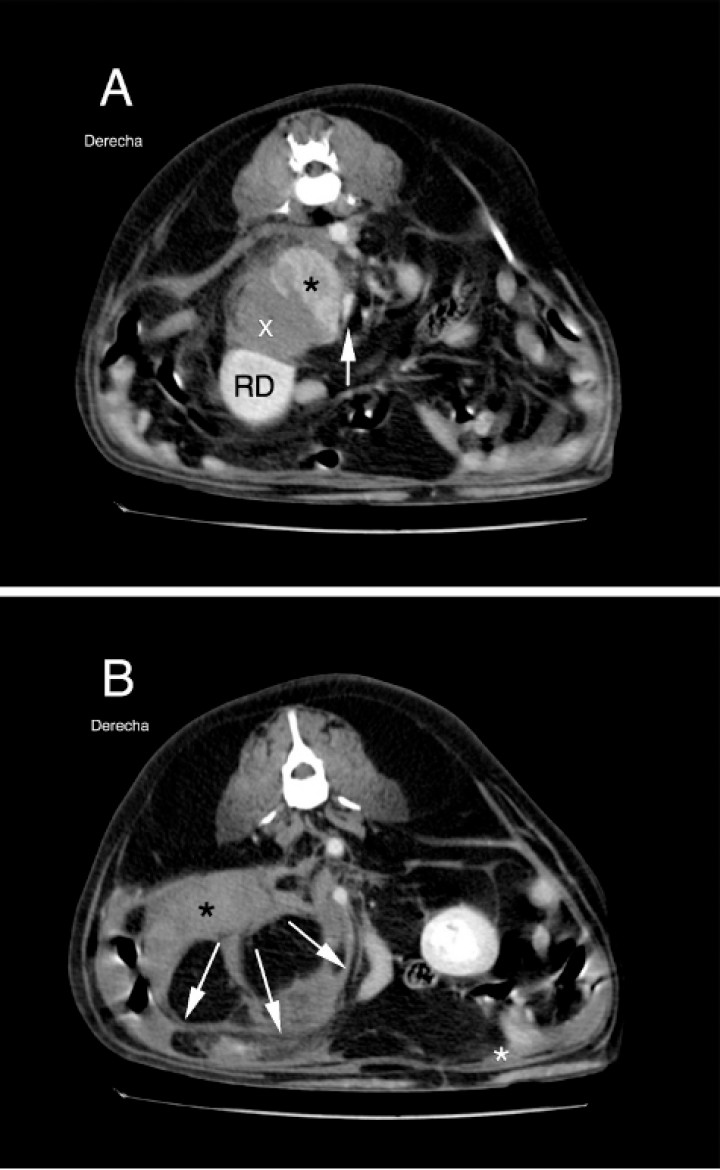

<p>Mismas imágenes que Fig.1. (A) Radiografía lateral derecha: señala posición del riñón derecho (RD), pérdida de definición de serosas a nivel retroperitoneal (entre flechas blancas) y a nivel peritoneal (asterisco blanco). (B) Radiografía lateral izquierda: muestra posición del riñón izquierdo (RI) y efecto masa desde zona retroperitoneal (flechas negras). (C) Radiografía ventrodorsal: señala posición de riñón izquierdo (RI) y masa mal definida localizada en la zona lateral derecha caudal a la última costilla y parcialmente superpuesta con la columna (flechas blancas), así como otra masa mal definida que ocupa gran parte del abdomen derecho caudal (flechas negras).</p>

Mismas imágenes que Fig.1. (A) Radiografía lateral derecha: señala posición del riñón derecho (RD), pérdida de definición de serosas a nivel retroperitoneal (entre flechas blancas) y a nivel peritoneal (asterisco blanco). (B) Radiografía lateral izquierda: muestra posición del riñón izquierdo (RI) y efecto masa desde zona retroperitoneal (flechas negras). (C) Radiografía ventrodorsal: señala posición de riñón izquierdo (RI) y masa mal definida localizada en la zona lateral derecha caudal a la última costilla y parcialmente superpuesta con la columna (flechas blancas), así como otra masa mal definida que ocupa gran parte del abdomen derecho caudal (flechas negras).

En las imágenes obtenidas por TC (Figs. 3 y 4) se observa una masa sólida en la glándula adrenal derecha con captación heterogénea de contraste (fase venosa), mostrando un valor medio de 24,4 UH (Unidades Hounsfield) antes del contraste y de 123,4 UH tras la administración de este (Iohexol, Omnipaque 350 mgI/ml, a dosis de 2,2 ml/kg, administrado manualmente). Dicha masa muestra continuidad y mantiene contacto con una masa ligeramente hiperatenuante (35 UH), la cual no muestra realce tras la administración de contraste y se extiende a través del retroperitoneo hasta la altura de L6. A su vez se visualiza una cantidad moderada de líquido libre retroperitoneal. La vena cava caudal se visualiza comprimida, parcialmente englobada y desplazada ventro-medialmente por la masa adrenal sin presentar defectos de llenado que sugieran la existencia de trombosis o invasión de su luz. El riñón derecho se observa desplazado ventro-caudalmente. Se observa una cantidad leve de líquido libre peritoneal.

Imágenes de TC post-contraste en plano transversal de la región abdominal obtenidas 20 segundos después de la administración de contraste y ventana de tejido blando (WW400, WL60), ordenadas de craneal a caudal. (A) Se observa masa adrenal de aproximadamente 3,9 cm (DV) x 3,4 cm (LL) x 3,6 cm (Cr-Cd) con captación heterogénea de contraste (asterisco negro), que mantiene contacto con vena cava caudal sin mostrar invasión intraluminal, desplazándola ventro-medialmente (flecha blanca). Hematoma adyacente (x) que desplaza riñón derecho (RD) caudoventralmente. (B) Se observa la presencia de acúmulo de líquido en zona retroperitoneal (asterisco negro) y, en menor cantidad, en zona peritoneal (asterisco blanco), así como el efecto masa de la zona retroperitoneal (flechas blancas).